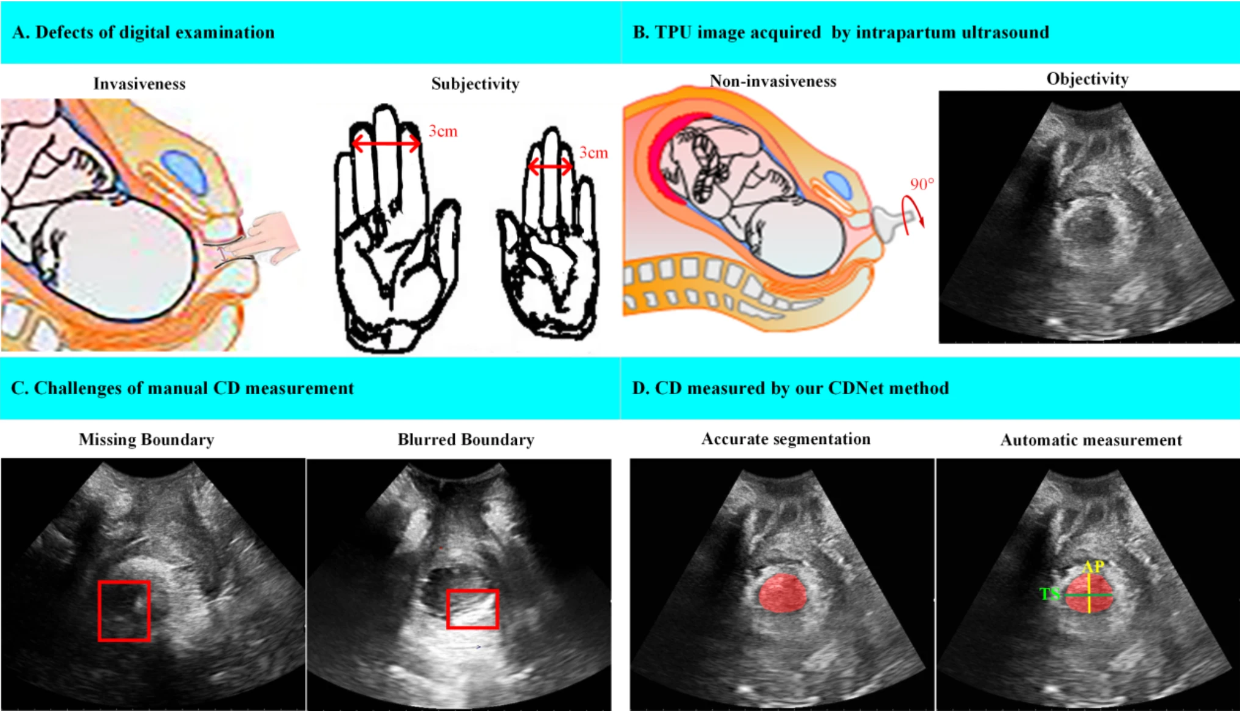

Accurate segmentation of cervix in intrapartum ultrasound images and measurement of cervical dilation (CD) are crucial for monitoring labor progress and predicting delivery outcomes. However, the poor quality of ultrasound images like artifacts and missing boundaries makes the measurement inaccurate and time- and effort-consuming. This paper proposes CDNet, a network for automatic measurement of CD. First, CDNet accurately segments the cervix mask, and then the center of the mask is located to find the horizontal and vertical intersection points to calculate the transverse diameter and anteroposterior diameter of CD. A shape-constraint loss function is used to improve segmentation accuracy by the prior convex shape. Experiments show that CDNet achieved the lowest Relative Volume Error of 15.56 ± 1.80%, the highest Dice of 89.55 ± 0.47%, and the lowest 95% Hausdorff distance of 11.48 ± 0.63 mm. The measurement of transverse diameter and anteroposterior diameter based on CDNet achieved a mean absolute error of 1.79 ± 0.24 mm and 2.67 ± 0.22 mm respectively. Moreover, CDNet also outperformed its counterparts in further experiments on two additional fetal head datasets. In conclusion, our method can achieve automatic CD measurement with good performance and may help assess labor progress in the future.